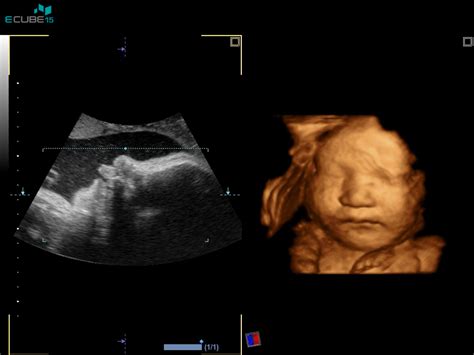

Plod se začne gibati že zelo zgodaj v nosečnosti, že okoli osmega tedna. Ti nežni gibi, kot so upogibanje in iztegovanje telesa ter nenadzorovani gibi okončin, so sicer nečutni za bodočo mamico, vendar jih je mogoče opaziti pri pregledu z ultrazvokom. Ko plod raste in se razvija, postajajo ti gibi vse izrazitejši in močnejši.